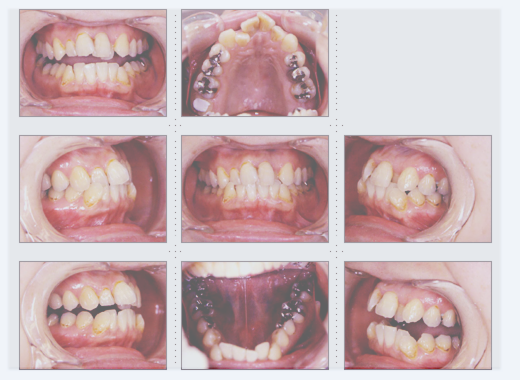

症例2

主婦 33才 女性

上下顎とも乳歯が残っており歯と歯の隙間が気になり、歯並びを奇麗にしたいとのご希望でした。

術後、家族や友人からもキレイになったと言われ、ご本人もご自分の歯のように気に入っていただけました。原因不明な頭痛もなくなり、快適な生活を送っていらっしゃいます。